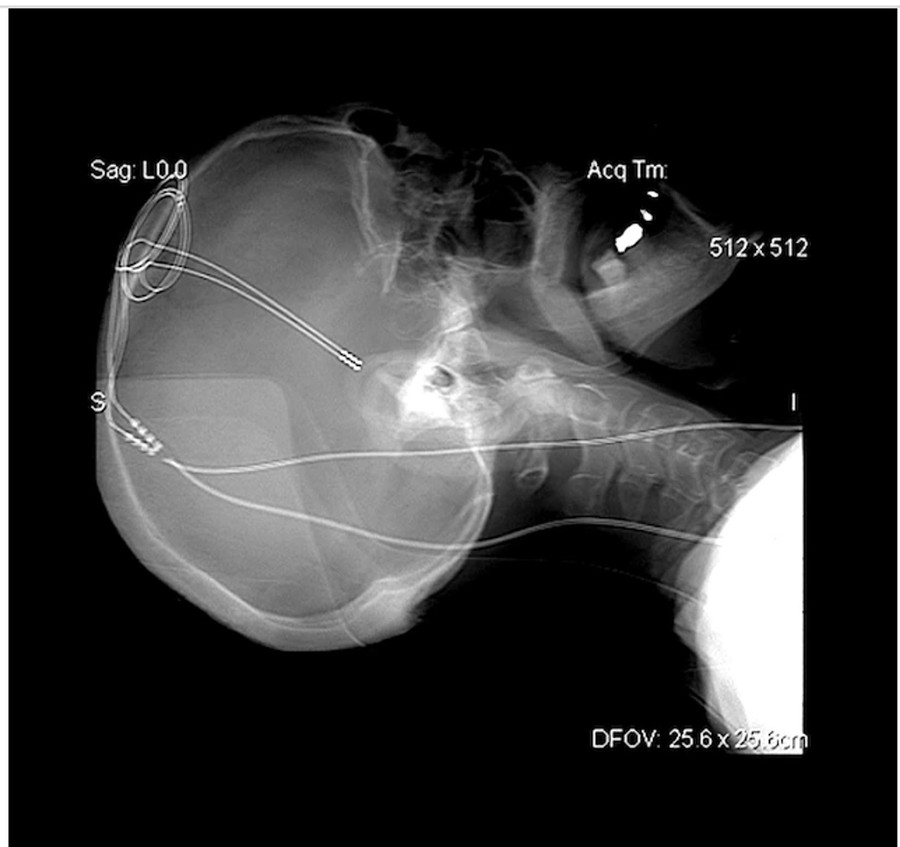

| Điện cực được phẫu thuật cấy sâu trong não để kích thích điện các tế bào thần kinh cụ thể để điều trị một số bệnh nhân bị động kinh. |